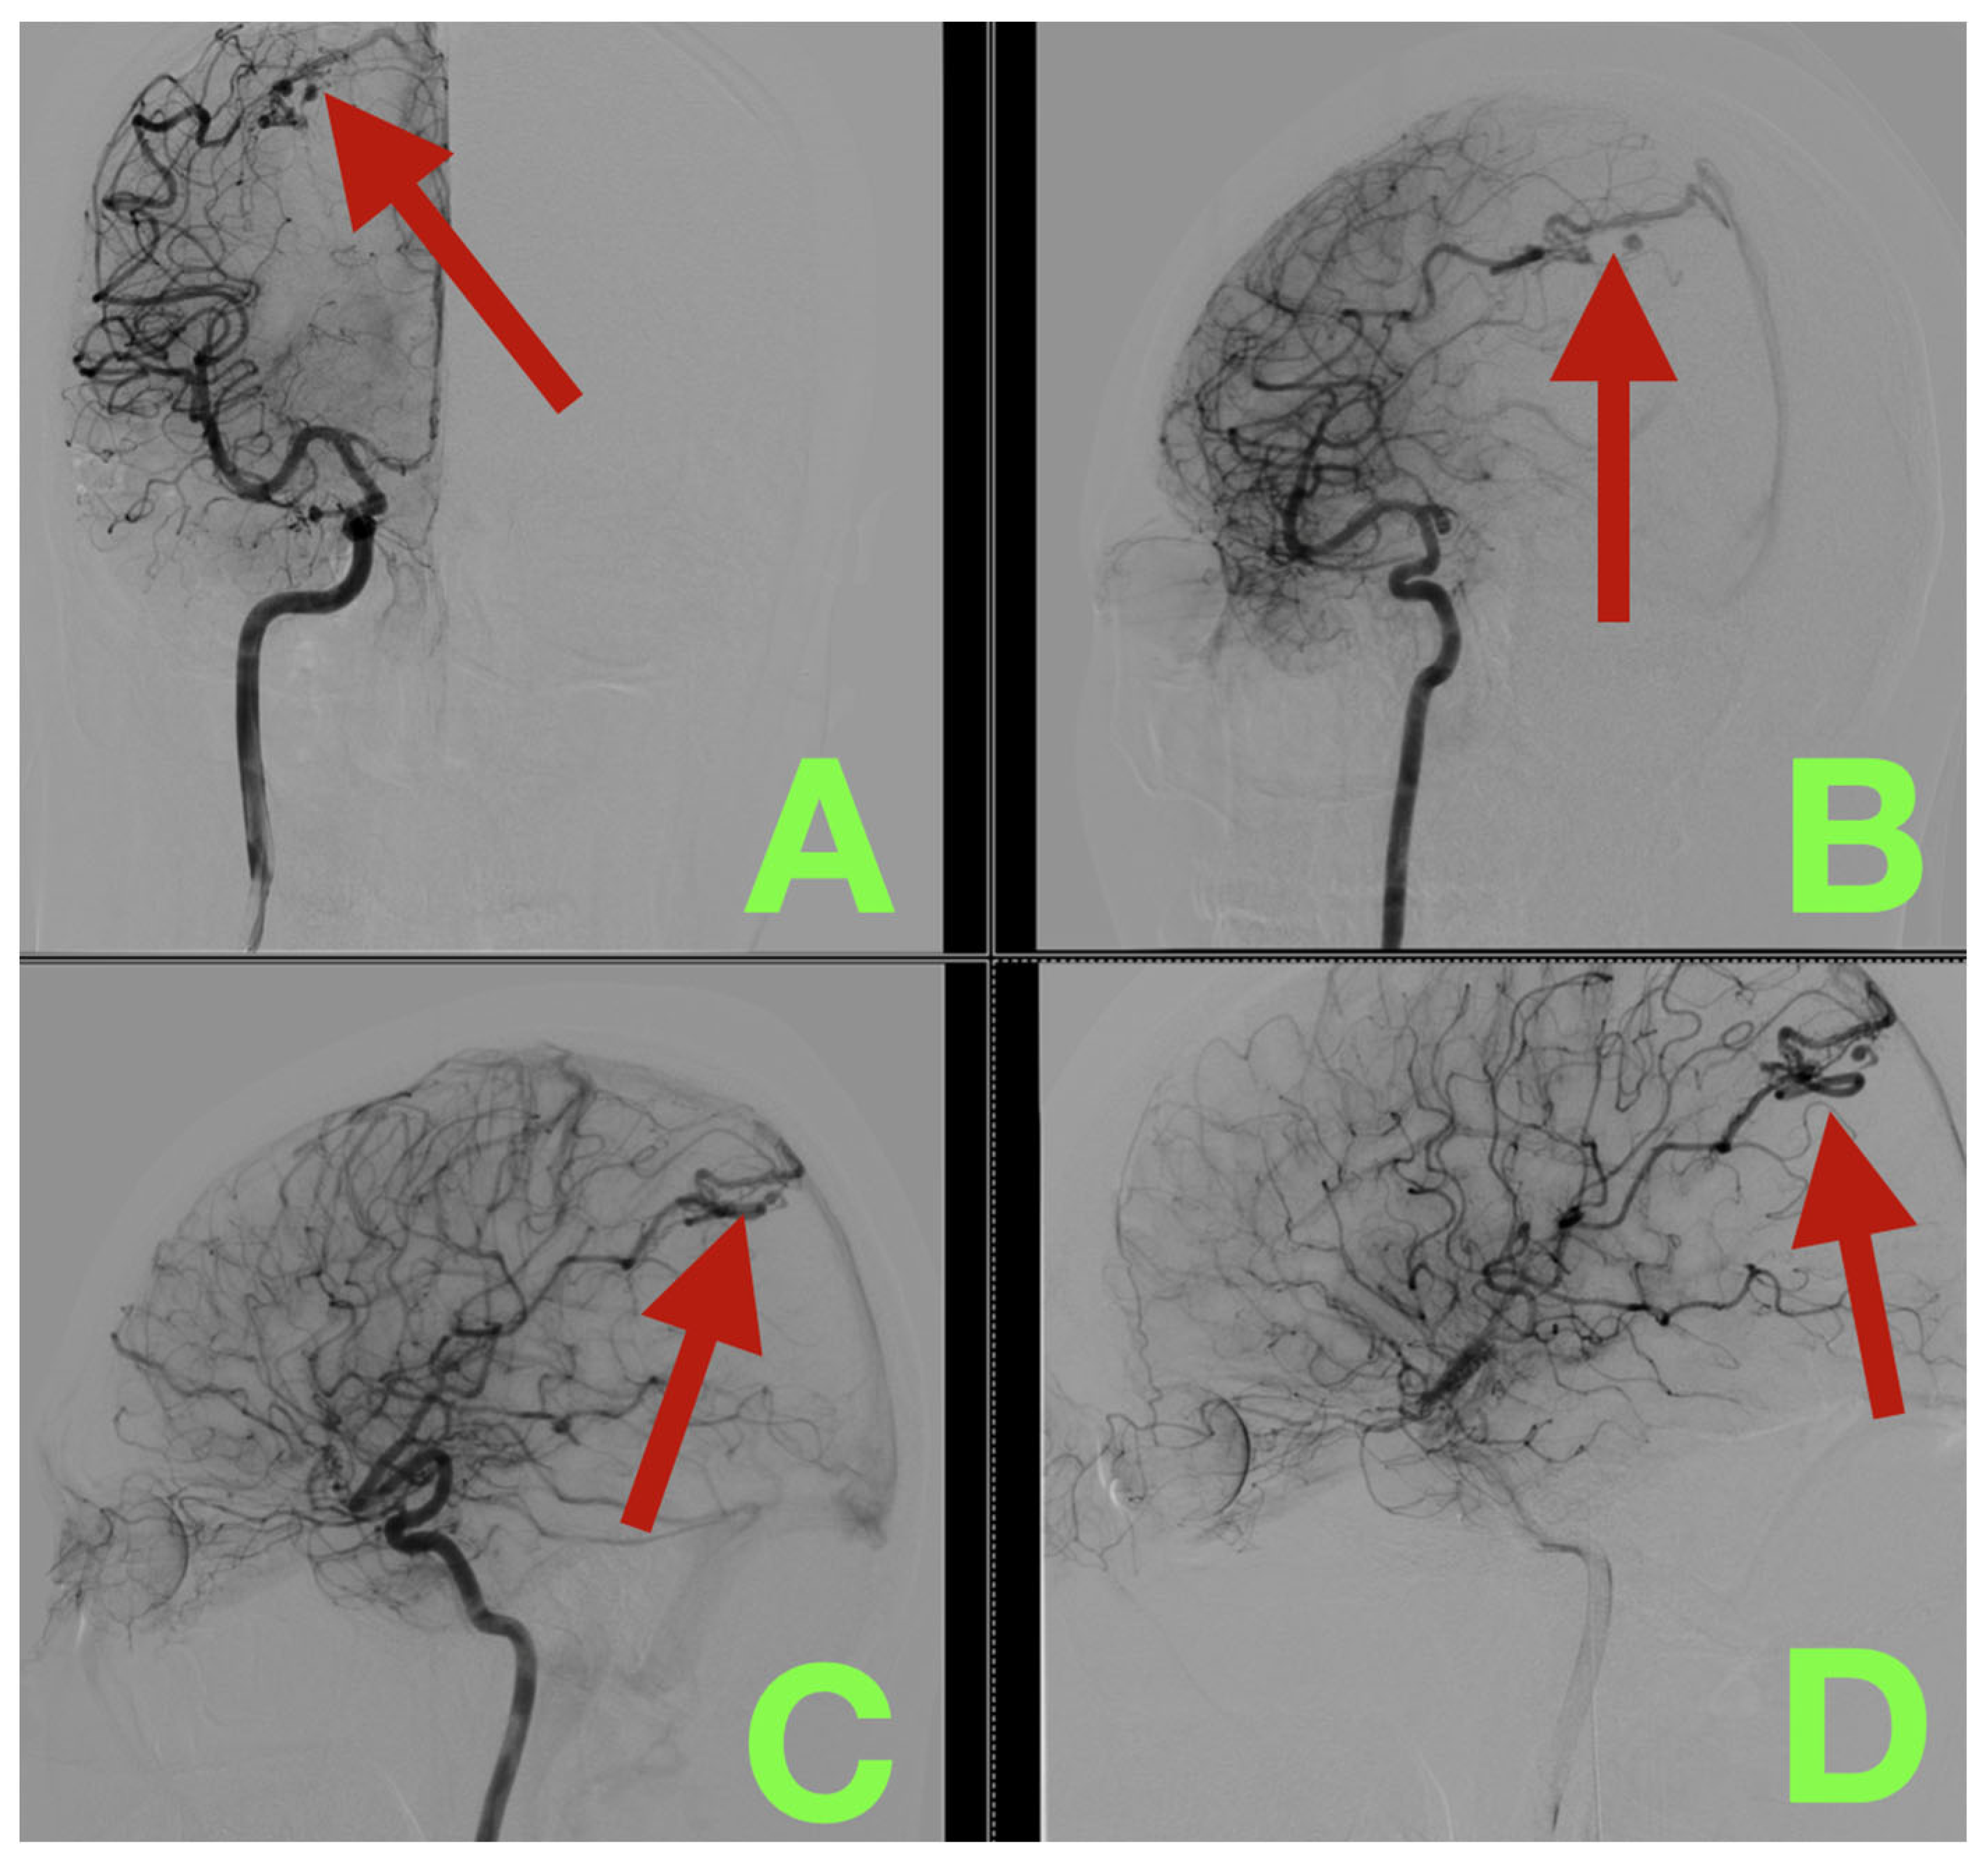

2. Case Presentation